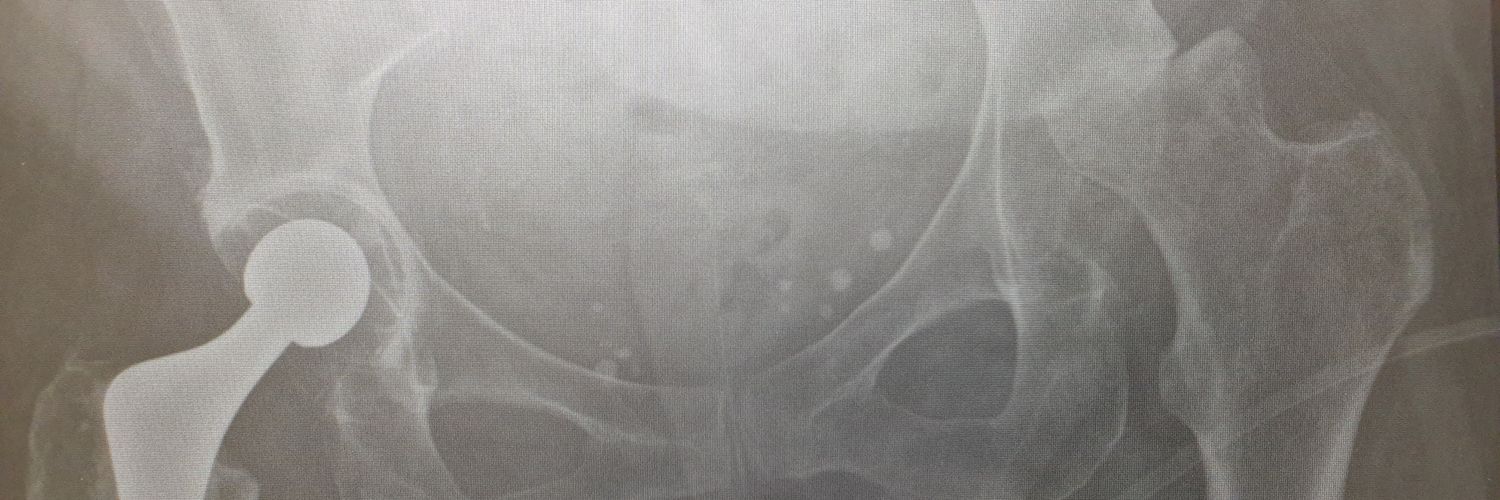

These are expensive too and a lot of hard work goes into getting pt on table. Thank you to YGC theatres & staff for the effort, @BetsiCadwaladr for support, fantastic MDT Wrightington, North Wales MDT, surgical experience @CavendishHip, my colleagues & Mr Kapur for dual operating